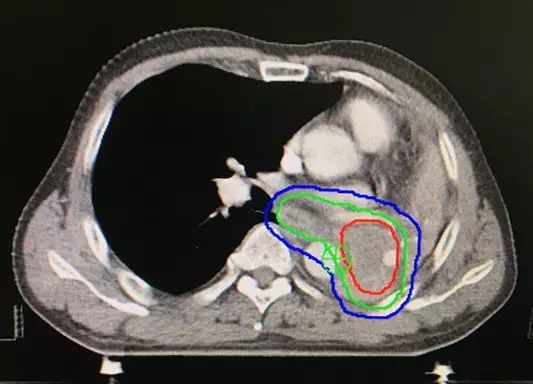

图3:放射治疗15次后,不张的肺组织完全复张